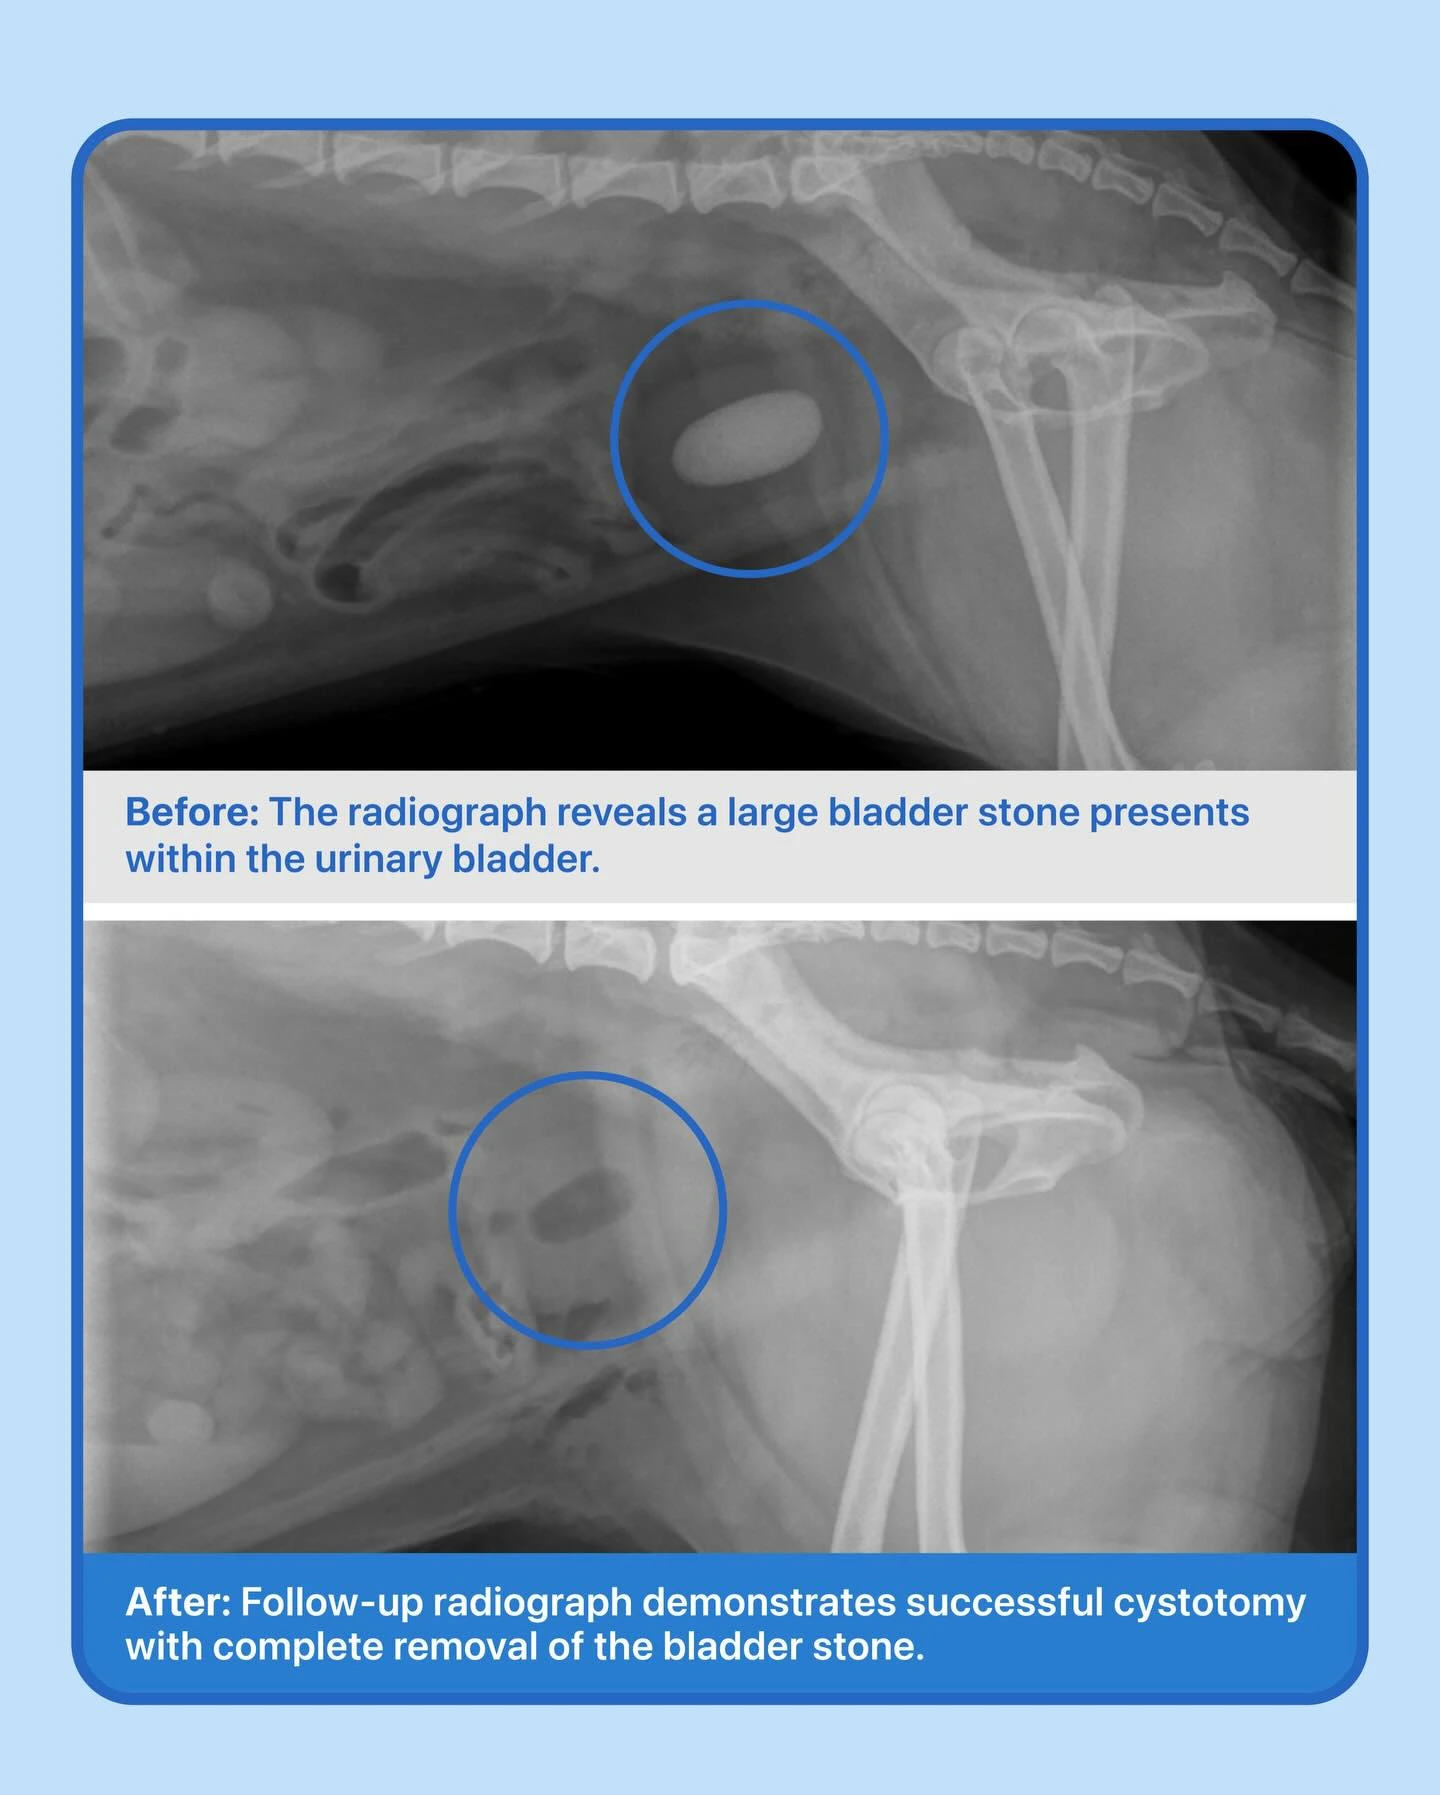

Cystotomy Success: Bladder Stones Removed!

This sweet pup came in for a bladder stone consult after an ultrasound at another clinic showed stones and surgery was recommended. After taking radiographs, we confirmed she needed a cystotomy, a surgery where the bladder is carefully opened to remove the stones and prevent further complications.

Everything went perfectly during surgery, and she’s healing very well at home with her family, enjoying a safe and comfortable recovery!